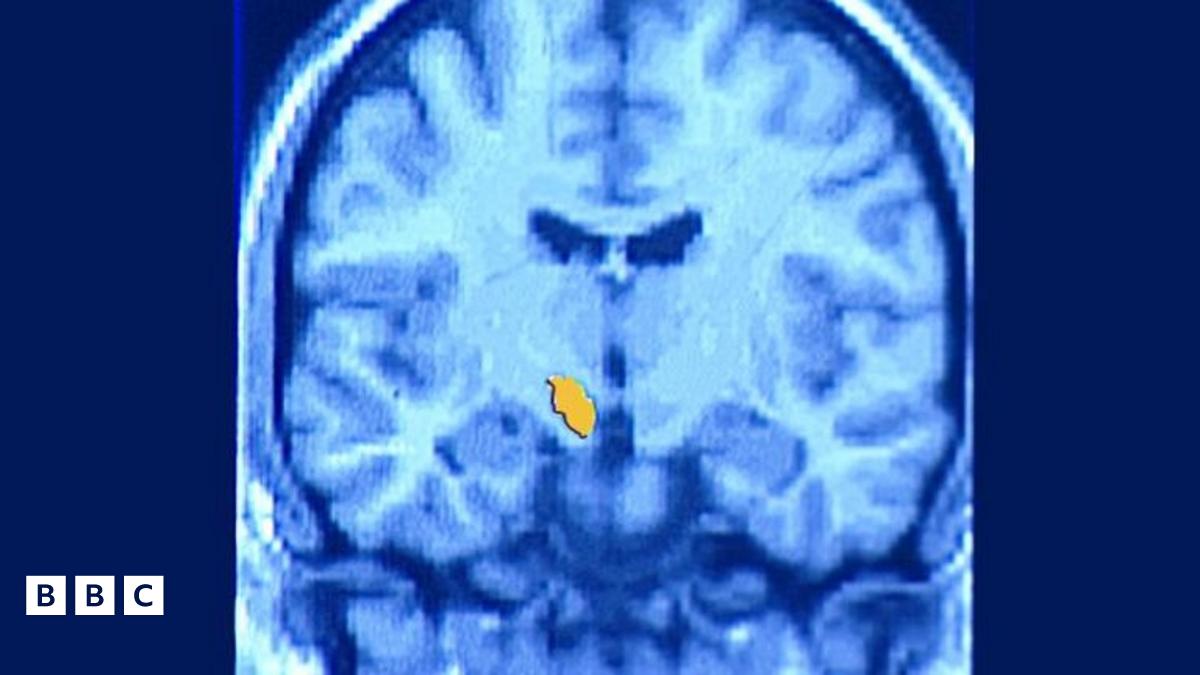

Cafwyd meddygon fod gan Mr Morgan affasia, anhwylder yr ymennydd sy'n effeithio ar iaith a chyfathrebu.

Mae'r cyflwr hefyd yn gallu achosi salwch o'r enw Syndrom Acen Estron sy'n achosi pobl i siarad ag acen o wlad arall.